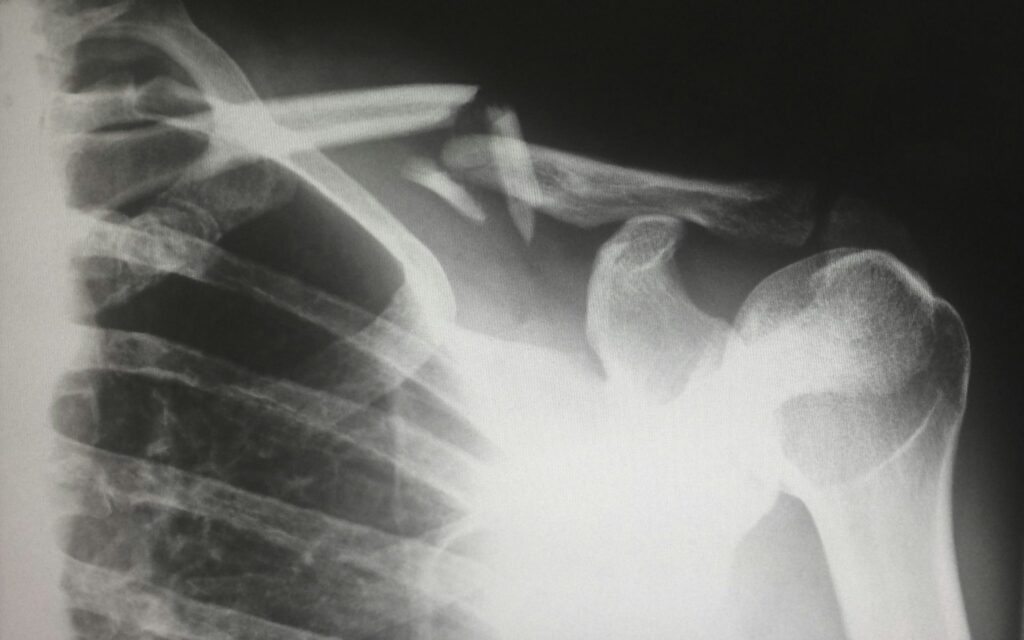

Анализът обхваща над 163 000 души от UK Biobank, проследени в рамките на повече от 12 години. Данните показват, че при увеличаване на дневния прием с около 3,7 порции ултрапреработени храни рискът от фрактура на тазобедрената става нараства с над 10%. Това е едно от първите мащабни изследвания, които директно доказват тази връзка при хора.